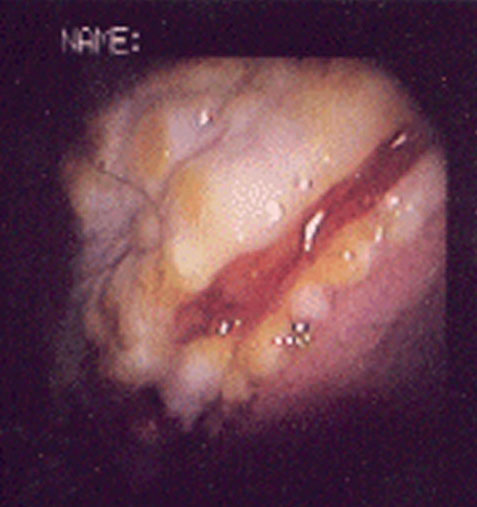

- 1 = Schleimhauterosionen: Hyperämie bzw. Hyperkeratose; oder oberflächliche Schleimhauterosionen.

- 2 = Leichte Ulzeration: Multifokale oder generalisierte Ulzerationsbereiche, die oberflächlich erschienen mit/ ohne Hyperämie und leichter/ mittlerer Hyperkeratose.

| Magenulkus-Index | 0 | 1 | 1 | 0 | 3 | 1 |

| Kommentar | keine Koliksymptome mehr | keine Koliksymptome mehr | Noch kleine Läsion mit Hyperkeratose | symptomfrei dem Besitzer zufolge | Keine Veränderung in den Symptomen | Bessere Leistung und ruhigeres Verhalten |